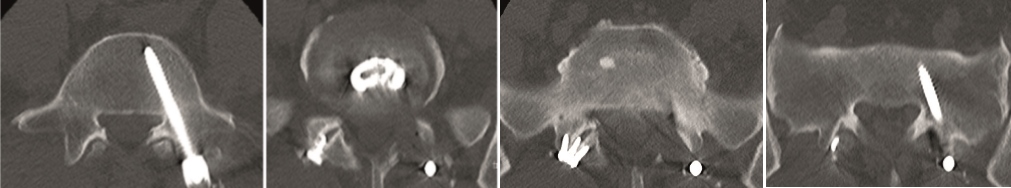

A female patient 66-years-old with back pain, leg pain, and degenerative deformity. The x-rays show left convex degenerative scoliosis Cobb T12-L3 38. Nonoperative treatment failed. Treatment option was posterior fusion T11-L5, with URS Facet Wedge L2-L3 unilaterally.

A conventional approach for posterior correction was taken, with indirect Foraminal decompression and Facet Wedge fusion (apex curve). Facet Wedge introduction after curve correction with rod in situ. X-ray follow-up initially (Fig 20), with CT assessment of Facet Wedge fusion after 6 months (Fig 21).